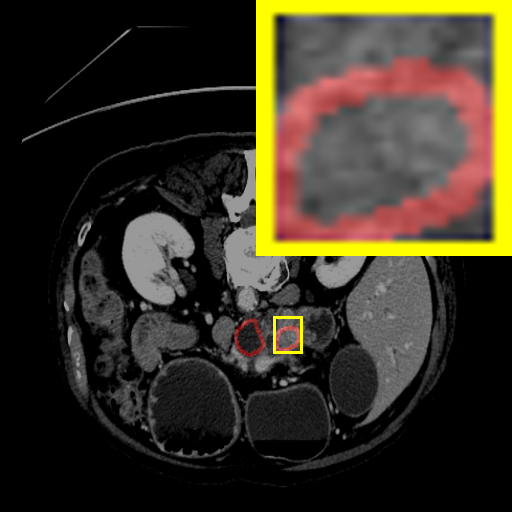

Figure 3: Qualitative comparison visualization of DEAP-3DSAM and baselines on four datasets.

IV-B2 Qualitative Performance Comparison

We also performed qualitative analysis on four datasets. As illustrated in Fig. 3, DEAP-3DSAM accurately identifies the target regions and closely matches their size. In contrast, 3DSAM-Adapter [3dsamadapter] exhibits limitations in matching the size and shape of the target regions. This proves that DEAP-3DSAM captures more complex image features, owing to its Dual Attention Prompter and Feature Enhanced Decoder. Furthermore, while these SAM-based methods are nearly capable of localizing the target regions, many traditional methods, i.e. UNETR++ [unetr++], Swin-UNETR [swinunetr], and TransBTS [transbts], struggle to achieve this. This highlights the potential of SAM-based methods for addressing complex 3D segmentation tasks.